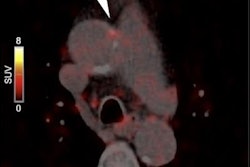

Three examples of Ga-68 FAPI uptake of active arterial segments. All three patients were over 60 years old with a history of hypertension and dyslipidemia. Patients A and C also had diabetes mellitus, and experienced myocardial infarction and percutaneous coronary intervention treatment. Patient A was obese (body mass index = 30) while patient B had a history of heavy smoking."To our knowledge, this is the first noninvasive study to describe the expression of FAP in the human arterial walls via Ga-68 FAPI-PET/CT imaging," they wrote.